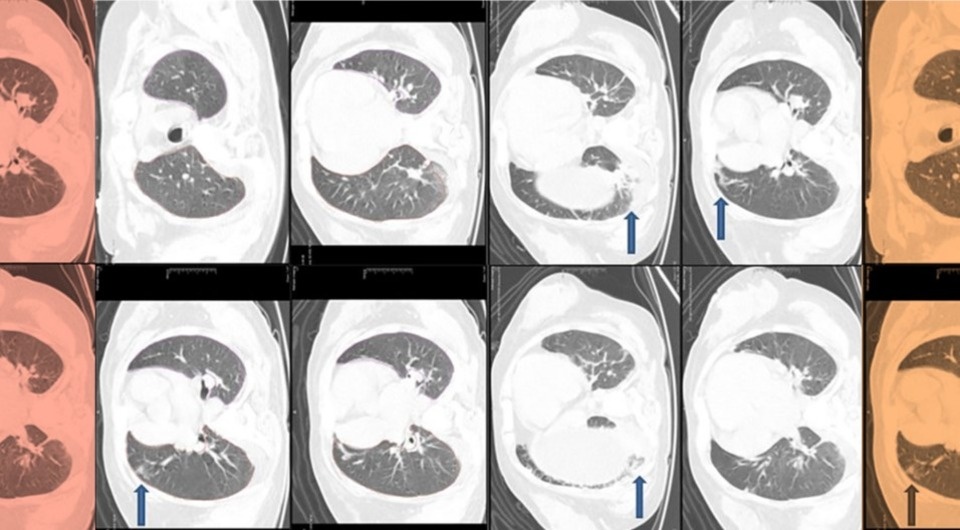

Анализ костного мозга подтвердил неэффективный эритропоэз без признаков злокачественности. Однако тяжесть клинических проявлений не соответствовала одному только дефициту питательных веществ. Ультразвуковое исследование брюшной полости выявило увеличение печени со стеатозом и циррозом. Аутоиммунные и инфекционные причины гепатита были исключены. На компьютерной томографии в обоих легких было отмечено диффузное помутнение по типу матового стекла с множественными фиброзными и ателектазными изменениями. Также врачи обнаружили вторичный гиперпаратиреоз с дефицитом витамина D и остеопорозом. Такой набор симптомов натолкнул врачей на поиск синдромальной генетической патологии.